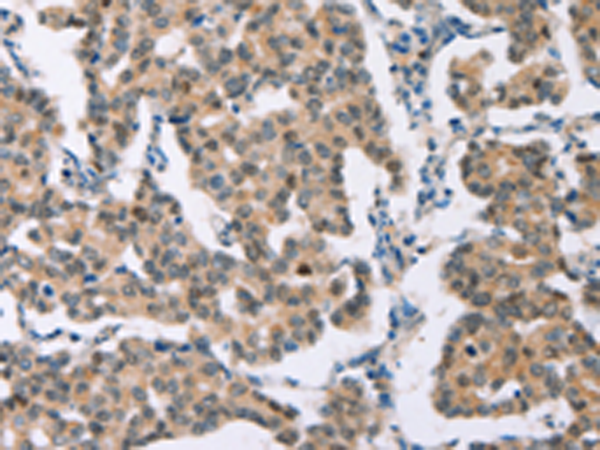

分类: 科研抗体货号: P11593别名: BAI1; GDAIF应用: IHC反应种属: Human, Mouse, Rat